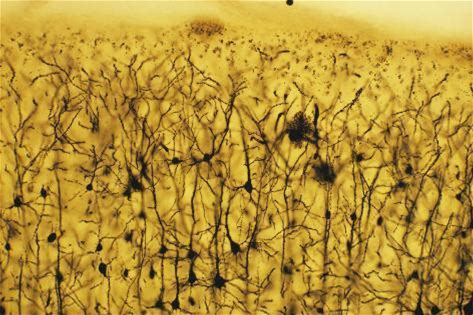

Poster: Cerebral Cortex Nerve Cells, 18x12in.